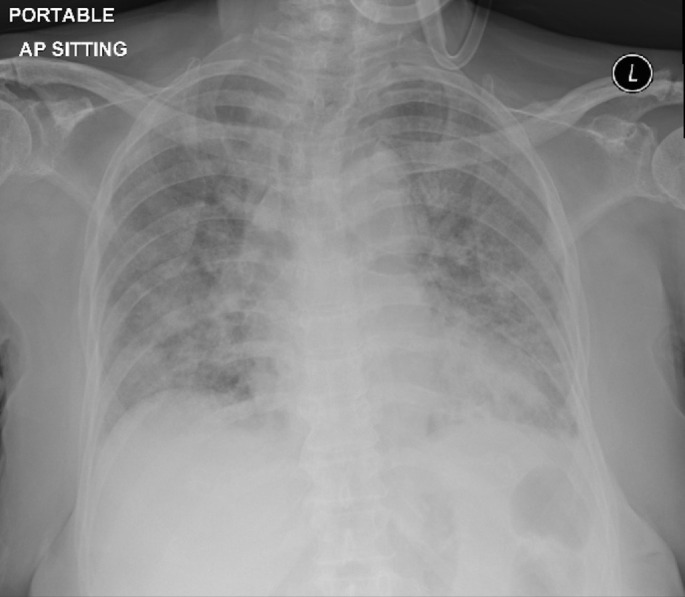

黏液表皮样癌是一种罕见的肺部原发性肿瘤。在仔细排除其他肺部肿瘤,尤其是那些组织学和放射学特征重叠的肿瘤后,可以做出诊断。https://bit.ly/4fcISSm。

Mucoepidermoid carcinoma is a rare primary tumour of the lung. Diagnosis can be made after careful exclusion of other lung neoplasms, especially those with overlapping histological and radiological features. https://bit.ly/4fcISSm.